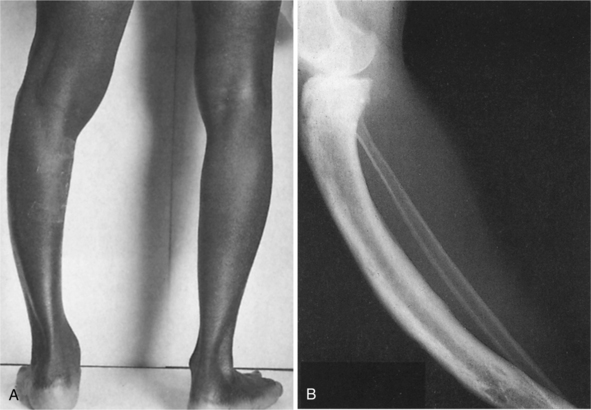

Clinical findings also include postural deformities such as increased thoracic kyphosis and bowing of the femurs and tibias (Fig. 24-10). Bony softening of the femoral neck can cause coxa vara (reduced angle of the femoral neck) and may result in a waddling gait. These changes may produce increased local mechanical stresses resulting in pain.

Figure 24-10 A, Bowing of the leg is often seen in Paget’s disease. B, Radiograph of a person with Paget’s disease affecting the tibia (but not the fibula). Overgrowth has resulted in an increase in length of the tibia, associated with bowing. Irregularity of both the periosteal and endosteal surfaces is shown. (From Bullough P: Orthopaedic pathology, ed 3, London, 1997, Mosby-Wolfe.)